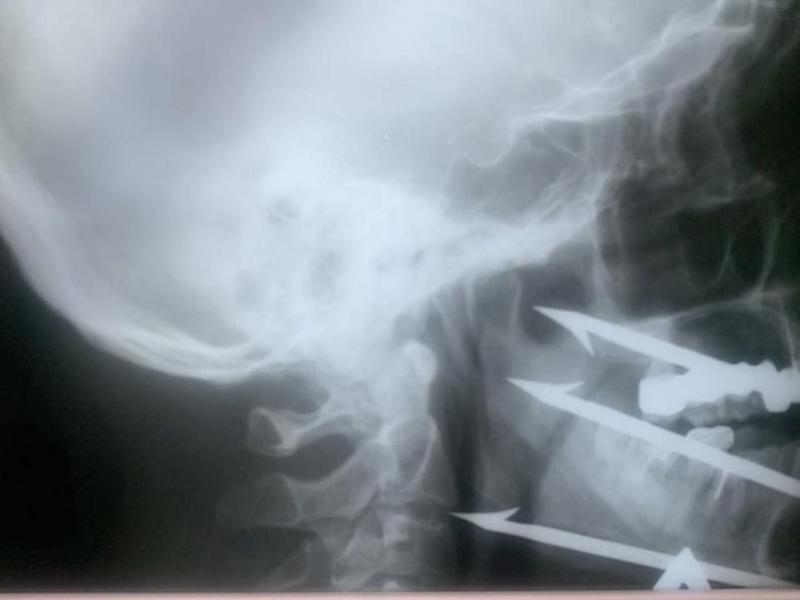

Инцидент произошел во время подводной охоты. Пострадавший был экстренно доставлен в Волгоградскую городскую клиническую больницу №1 с критическим состоянием: трехзубый гарпун глубоко вошел в лицевые ткани.

Ситуация была крайне опасной: острие гарпуна остановилось всего в миллиметре от сонной артерии. Любое неосторожное движение, смещение или ошибка могли привести к моментальной гибели пациента.